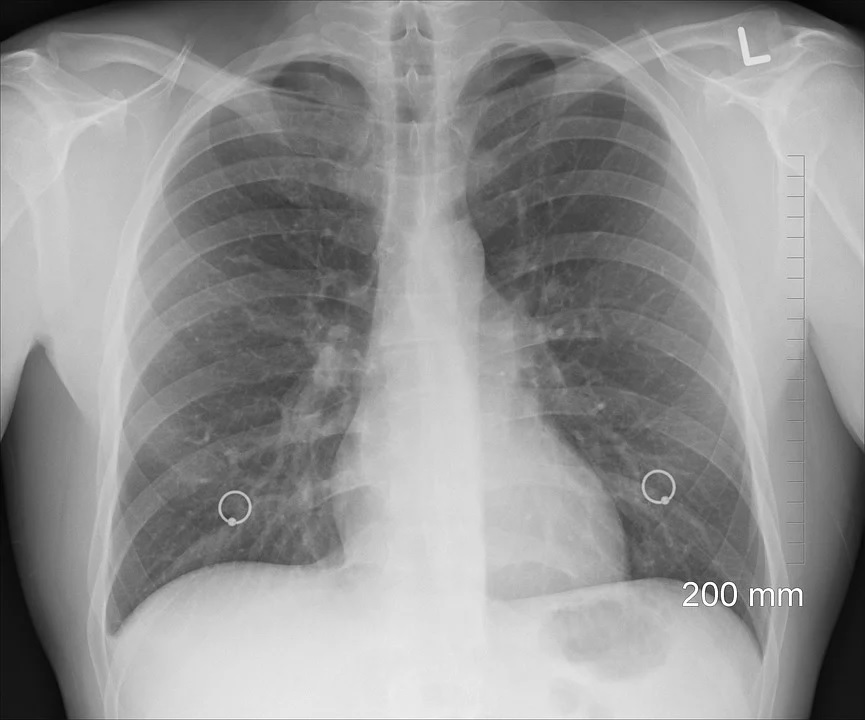

«Очаговый туберкулез диагностирован у 2 человек, инфильтративный – у 9 человек, диссеминированный – у 5 человек, туберкулема – у 2 человек, туберкулез внутригрудных лимфатических узлов – у 2 человек, костно-суставной туберкулез – у 1 человека», – сообщают представители Сердобской больницы на своей странице в соцсети.

Светлана Кутыркина отмечает, что у 13 человек из 21 установить диагноз на ранней стадии помогло флюорографическое обследование.